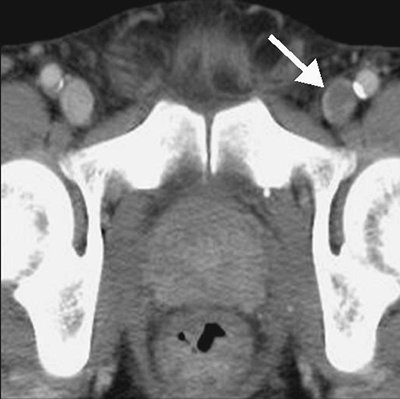

FIGURE 17-20. Deep venous thrombosis. CTV shows intraluminal filling defect within the left femoral vein (arrow).

FIGURE 17-21. Deep venous thrombosis. A: CTV of a 42-year-old man with protein C deficiency and recurrent DVT shows a filling defect within a left pelvic vein (arrow). B: CTV at a more inferior level shows thrombus within the left femoral vein (arrow).